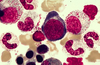

How old is this patient? Where is the megakaryocyte?

To whom, how old, would this marrow be hypoplastic? What are some causes of hypoplasticity?

This marrow would be hypoplastic to anyone below 40. Causes: toxins, viral infection, fanconia anemia (congenital), myelodysplastic dynrome, paroxysmal nocturnal hemoglobinuria. EBV, CBV, parvovirus, idiopathic.

What are the large cells? Are they increased in number?

The large cells are megakaryocytes, and they increased in number.

What are the two large cells? What are the small “black” cells. Which cells are more mature?

The two large cells are two megakaryocytes. The dark black could be lymphocytes or darkly nucleated RBCs. As a cell matures, it gets smaller and the Nucleus:Cytoplasm ratio decreases.

How can you tell that you’re in the bone marrow? Which cell is the pro-erythroblast? What is a nurse cell?

Bone marrow = lots of cell types in different stages of development. The pro-erythroblast is the big, dark purple cell with little cytoplasm. Nurse Cells are macs that have Fe that is transferred to surrounding immature RBCs.